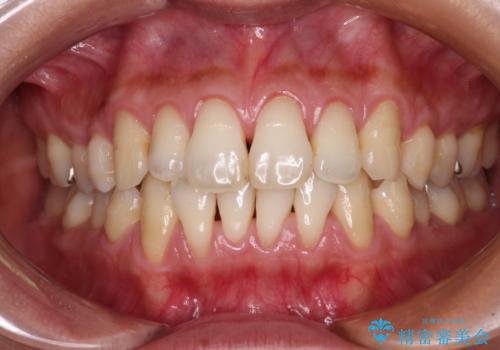

- 年々歯肉退縮が進行することを気にして来院された患者様です。

歯肉が菲薄であることが経年的な進行の原因であることが推察されたため、上顎からの結合組織移植術(CTG)により、歯根の被覆を行うとともに、歯肉の厚みを増すことで将来の退縮リスクを抑制することとしました。